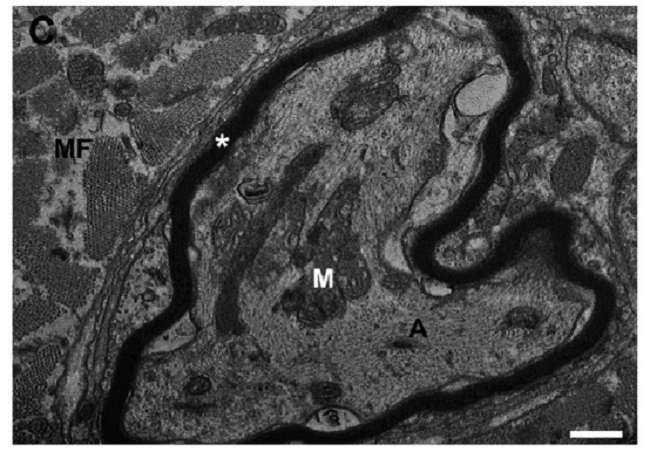

The methanolic extract of R. schneideri poison did not affect muscle morphology suggesting absence of myotoxic effect; however, the extract exhibits a neurotoxic action, since remodels the nerve terminals and the intramuscular motor innervation in PND preparation. Figure 2 illustrates and describes such effects.